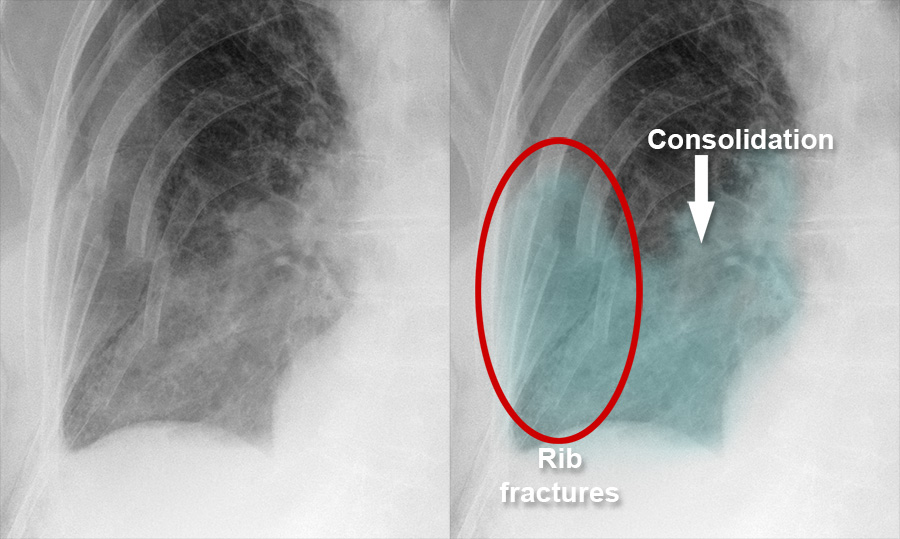

Chest Xray Pulmonary disease Lung contusion and haemorrhage